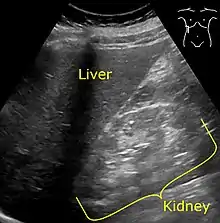

Ultrasonography showing hyperechogenicity of the renal cortex, visualized in the image as brighter than the liver.

It is recommended that diabetics have their albumin levels checked annually, beginning immediately after a diagnosis of type 2 diabetes and five years after a diagnosis of type 1 diabetes.[15][18] Medical imaging of the kidneys, generally by ultrasonography, is recommended as part of a differential diagnosis if there is suspicion of urinary tract obstruction, urinary tract infection, kidney stones or polycystic kidney disease.[19] Conformation kidney biopsy should only be performed if non-diabetic kidney disease is suspected.